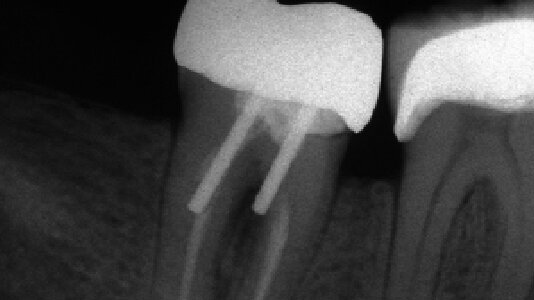

Klinické studie rovněž jednoznačně nepodpořily názor, že čepy posilují endodonticky ošetřené zuby.2, 10, 25, 26 Při zkoumání 200 RTG snímků pacientů, kteří před několika lety prodělali endodontické ošetření, bylo zjištěno, že zuby s čepy trpěly významně častěji apikální periodontitidou.2 Analýza údajů z různých klinických studií odhalila, že u 3 % zubů s čepy došlo k fraktuře a nenalezla žádný důkaz o tom, že by čepy přispívaly k delšímu zachování zubů.26 Čepy měly malý vliv na zlepšení klinické úspěšnosti pilířů fixních náhrad. Při srovnání klinické životnosti endodonticky ošetřených sponových zubů neopatřených kořenovými čepy s klinickou životnosti zubů stejné kategorie avšak se zavedenými kořenovými čepy se zjistilo, že tyto mají daleko delší životnost, což se projevilo i delší životností souvisejících částečných snímatelných náhrad.10

Přestože krátké čepy nebyly nikdy prosazovány, studie prokázaly, že je lze na RTG snímcích vidět poměrně často (obr. 3). Bylo zjištěno, že pouze 34 % z 327 čepů bylo délky shodné se incizo-cervikálním rozměrem zubu.46 Při hodnocení 200 endodonticky ošetřených zubů se zjistilo, že pouze 14 % čepů odpovídalo dvěma třetinám nebo více délky kořene.47 Další studie RTG snímků 217 čepů zjistila, že pouze 5 % čepů odpovídalo dvěma třetinám až třem čtvrtinám délky kořene.48 Fraktury kořene způsobené vysokou zátěží se objevovaly častěji v případech použití krátkých čepů,23, 49–52 přičemž s narůstající délkou čepu narůstala také odolnost kořene vůči zlomení.21